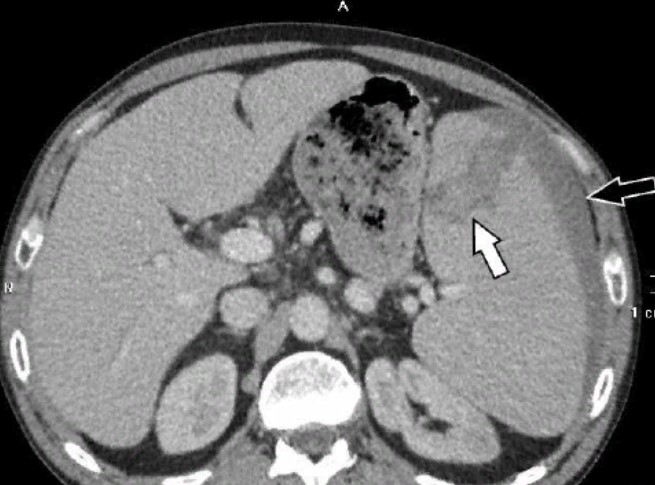

Интраренальная лоханка: рентгеновские снимки и примеры

Раздел: Фотоэссе